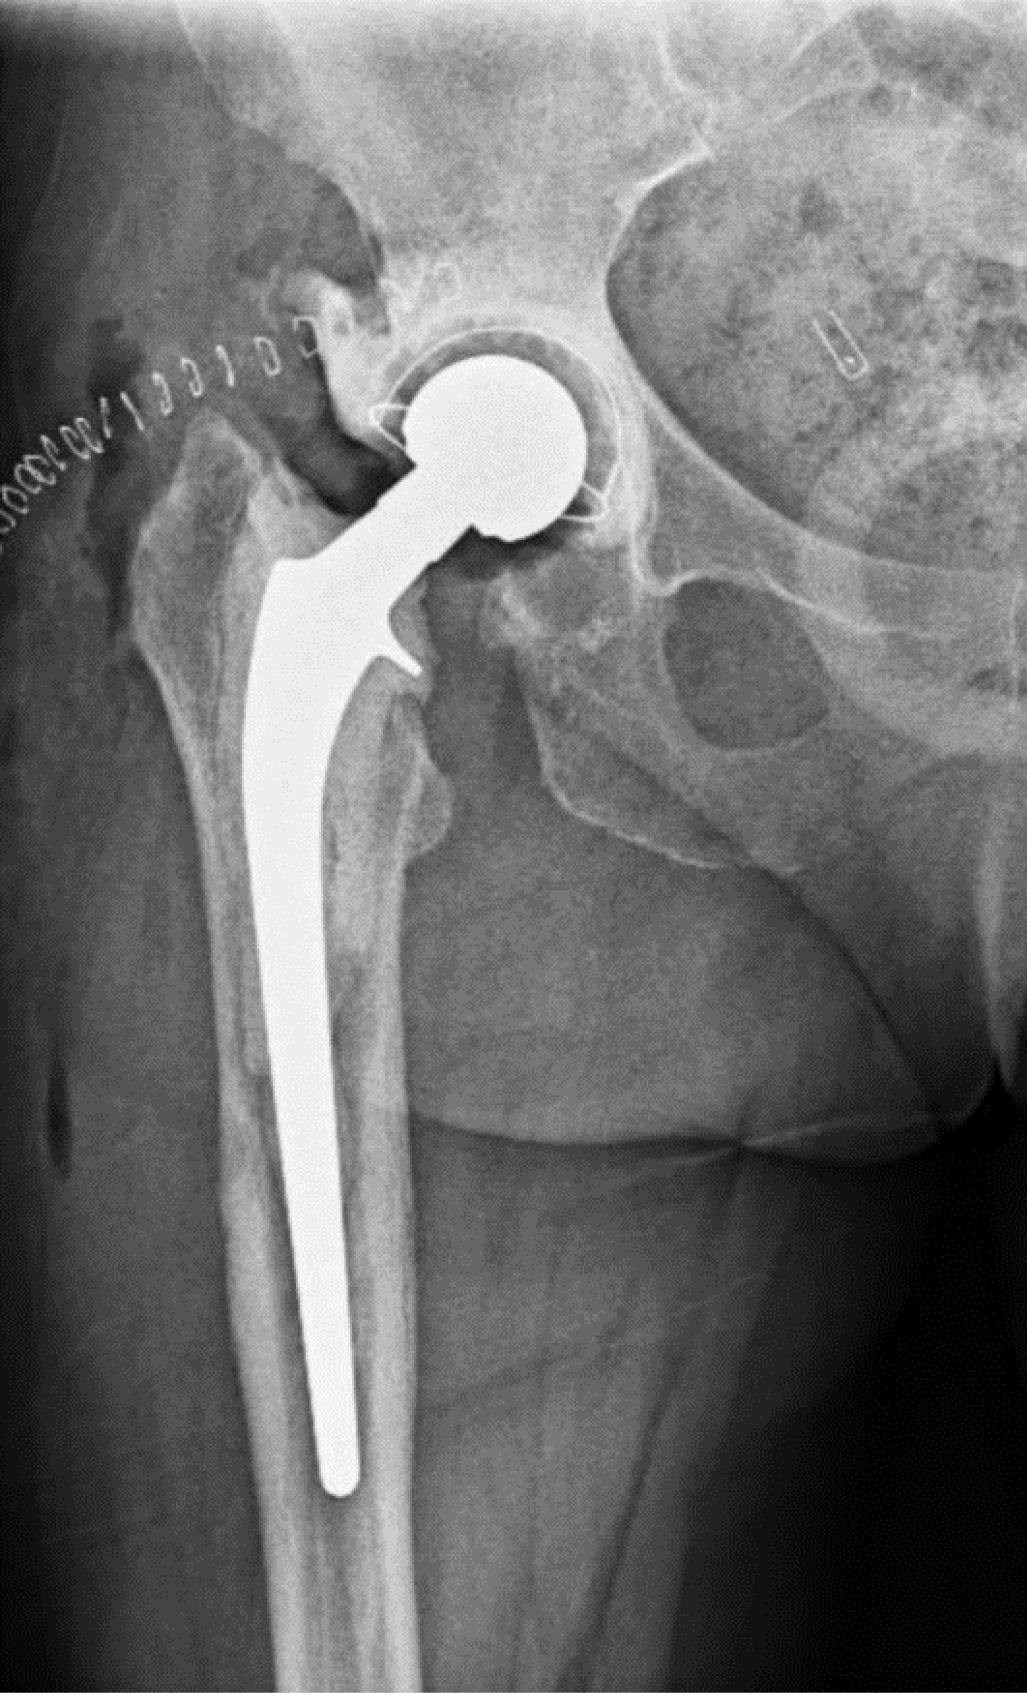

This study involves two consecutive cohorts. In the first cohort, from 2017 to 2020, only Girdlestone (Figure 1) intervals were used (Group A). At the beginning of this period, gentamicin beads were left in place during the first-stage surgery and were removed 2 weeks later. Patients were instructed to avoid weight-bearing during the interim period to limit leg length discrepancy. Antibiotic treatment was discontinued for at least two weeks before the second-stage procedure. After reimplantation, patients received intravenous antibiotics for five days, which were discontinued if cultures remained negative on day five. If cultures were positive, patients received an additional course of targeted antibiotic therapy for at least six weeks.

In the second cohort, from 2020 to 2023, a new protocol was introduced in our center (Group B). After the resection arthroplasty, a CUMARS (Figure 2) was created by coating commonly used femoral and acetabular components (Link® Lubinus Classic Plus Stem and Link® IP Acetabular Cup (Waldemar Link GmbH & Co. KG, Hamburg, Germany)) with antibiotic-loaded cement (Palacos® R+G bone cement, Heraeus Medical GmbH, Wehrheim, Germany), with additional antibiotics (1 g per batch of cement) tailored to the patient's specific pathogen (Figure 3). The spacer was then loosely implanted when the cement had a doughy consistency, ensuring easy removal during the second-stage surgery. Rotational stability of the CUMARS is achieved by folding the cement around the edges of the proximal femur and acetabulum. Patients were permitted partial weight-bearing (up to 50% of bodyweight) during the interval based on a recommendation by the operating surgeon. Patients were continuously treated with a minimum of 6 weeks of antibiotics following the first-stage surgery, including 2 weeks intravenously, up until reimplantation. After reimplantation, they received an additional 6-week course of antibiotics, with 1 week administered intravenously, totaling a minimum antibiotic duration of 12 weeks in total. In Group B, a Girdlestone interval was used in case a CUMARS was deemed contraindicated by the treating orthopedic surgeon intraoperatively based on bone stock and fracture risk. These patients received antibiotic treatment according to the protocol used in Group A.